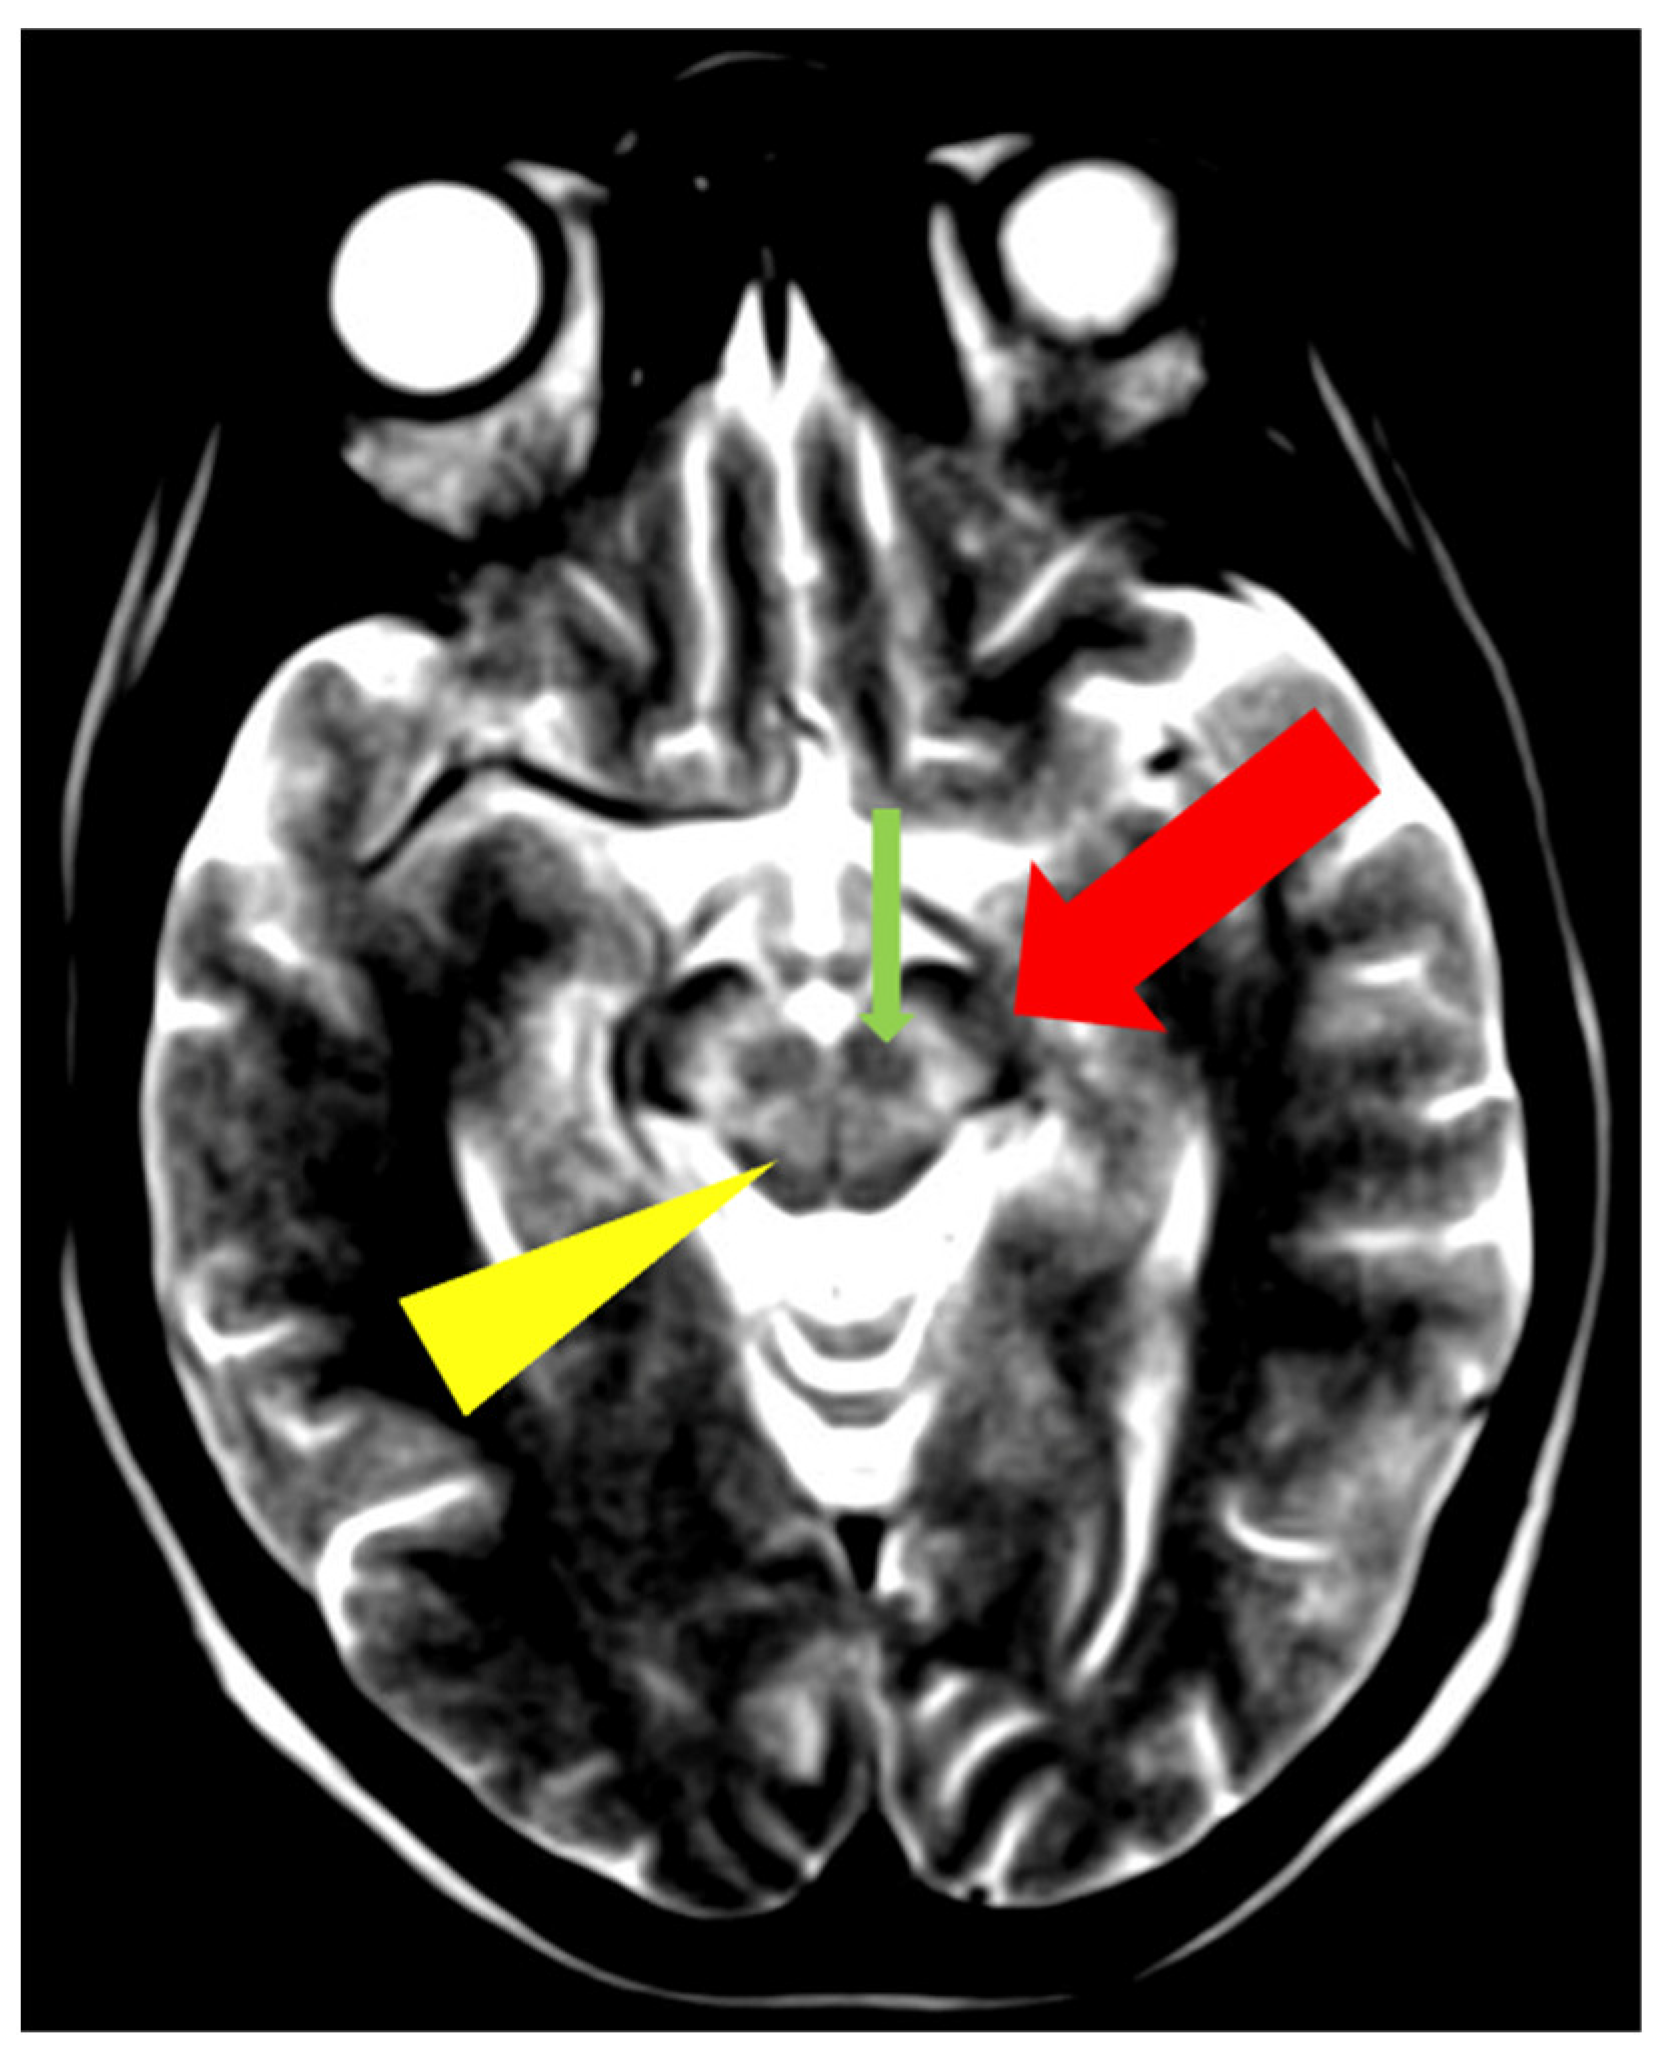

In addition to typical and frequently encountered features among patients with WD, especially in its neurological form, hyper- and hypointense changes in deep brain structures in T2, T2*, FLAIR, and SWI sequences on brain MRI have been noted [10]. Hyperintense foci in the midbrain and pons may sometimes occur in a characteristic pattern with normal brain tissue. Characteristic signs include the ‘face of the giant panda’ in the midbrain and the ‘miniature panda’ sign in the pons, which are considered so-called pathognomonic neuroradiological signs of WD. Besides the aforementioned abnormalities, other pathognomonic signs in WD include the bright claustrum sign, split thalamus (onion sign), and whorl sign [71].

The ‘face of the giant panda’ sign is characterized by an area of increased signal intensity in the midbrain tegmentum and hypointense red nuclei (panda’s eyes), the substantia nigra forming a reticular structure (panda’s ears), and hypointense signal in the superior colliculi (panda’s chin) (Figure 7) [71,72]. The ‘miniature panda’ sign is observed in the pontine tegmentum and consists of hypointense medial longitudinal fasciculi and tegmental tracts (panda’s eyes), hyperintensity of the aqueduct opening into the fourth ventricle (panda’s nose and mouth), with the superior cerebellar peduncles forming the panda’s cheeks (Figure 8) [71,72]. It may appear independently or in conjunction with the ‘face of the giant panda’ sign. In T2 and FLAIR sequences, the presence of a hyperintense internal medullary lamina between the medial and lateral groups of thalamic nuclei has been noted—the split thalamus sign arises from the internal medullary lamina system with significantly increased signal intensity separating the medial and lateral thalamic nuclei with higher signal intensity but lower than the internal lamina (Figure 9) [73]. The whorl sign arises in the putamen due to the coexistence of several concentrically arranged hyperintense bands [15] (Figure 10). The bright claustrum sign arises from the increased signal intensity in the claustrum [74] (Figure 11). In the publication by Su et al., another neuroradiological sign was presented using 7T SWI brain MRI. The hyperintense globus pallidus rim sign was defined as a linear pseudohyperintense signal at the lateral border of the globus pallidus, resulting from the hypointense signal of the globus pallidus and putamen [75].

Figure 7.

The ‘face of the giant panda’ sign—increased signal intensity in the midbrain tegmentum and hypointense red nuclei (thin arrow), the substantia nigra (thick arrow), and hypointense signal in the superior colliculi (arrowhead) (own materials of the neurology department).